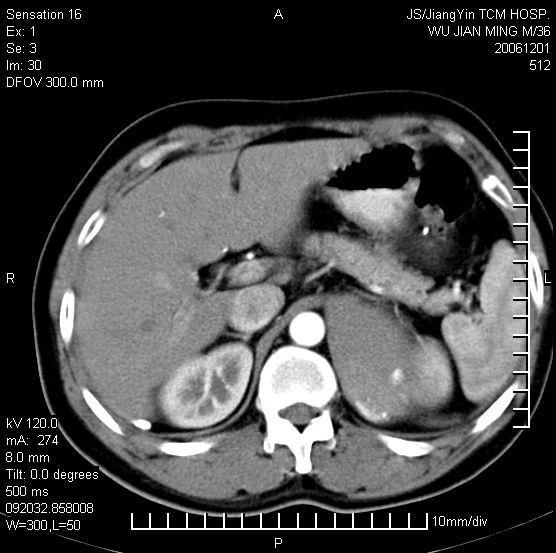

以下是引用dyqct在2006-12-1 21:17:00的发言:[br]左心缘旁及后肋膈窦区见巨大椭圆形混杂密度肿块,周围见大小不等斑片状钙化,内部无强化,周围包膜轻度强化,心脏明显受压变形,即明显占位效应,肿块广基与心包、膈相连。肝、脾内、肝门见多数小结节状钙化影。[br]考虑:1、左心缘旁及后肋膈窦区慢性包裹性胸膜炎(结核性);[br] 2、肝、脾及肝门淋巴结核已钙化。[br]

以下是引用zyx168在2006-12-2 10:10:00的发言:[br][br]肝脾肺内多发钙化灶